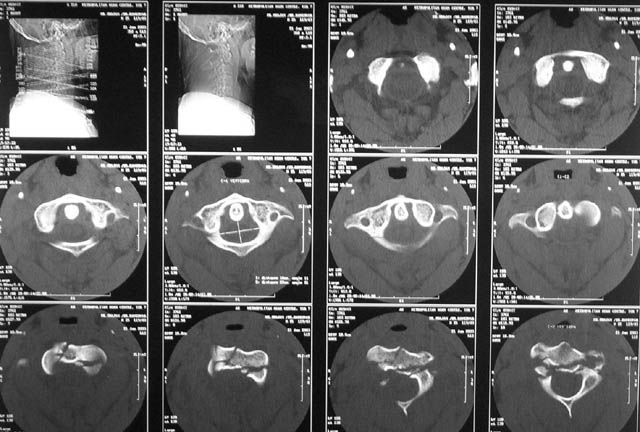

At our centre: Haemodynamically stable. Grade III compound fracture left femur with a wound anteromedially in the middle thigh through which the femur had come out. Distal pulse present. Cervical spine - C1 post ring fracture right side. C2 fracture body with listhesis. No canal compromise. No neurological deficits clinically.

X rays and CT film attached. We have put the patient on skull traction and posted him for debridement and proceed ----. What we have done I would like to present after the discussion.

The skull traction is being continued. My colleague, Dr K P Ramkumar, Chief of our Spine unit, said that the the cervical injury belongs to Levine type II and most probably it will be conservative management only. However he wants to repeat the x-ray on traction after a few days and do also a dynamic flexion and extension view. The need for surgical intervention will be decided after this. He also feels that patient has a subjective numbness of finger tips and mild grip weakness. According to him this indicates that the spinal cord had minimal trauma.

The cervical spine x-ray done on traction in neutral, extension and flexion. Images attached. Request comments.

txn extension

txn neutral

txn flexion